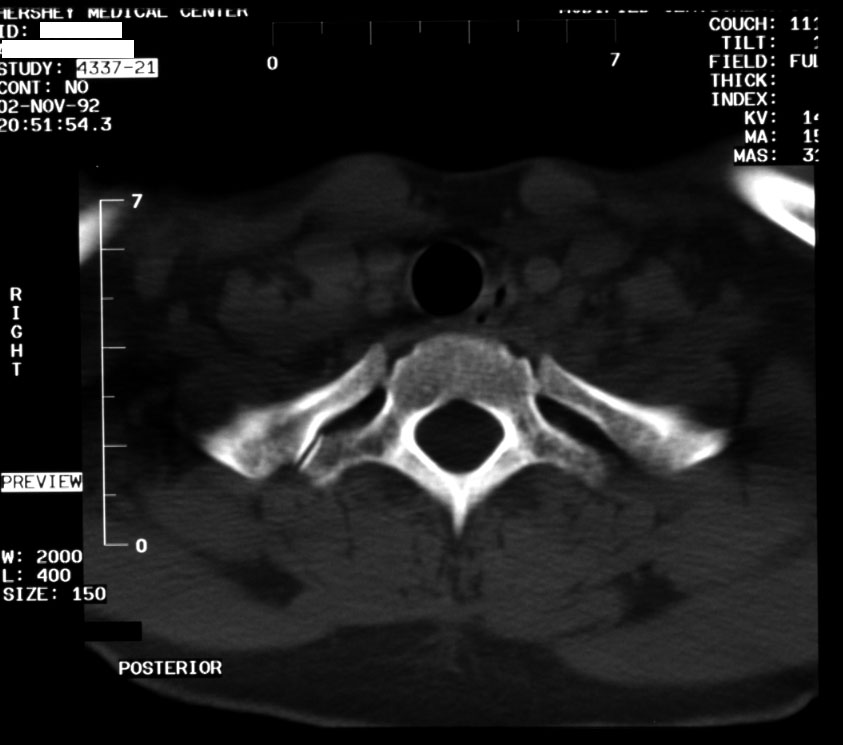

Normal Thoracic Spine (axial CT) -- Identify: vertebral body, pedicle,

lamina, spinous process, transverse process, rib costotransverse joint,

spinal canal, trachea